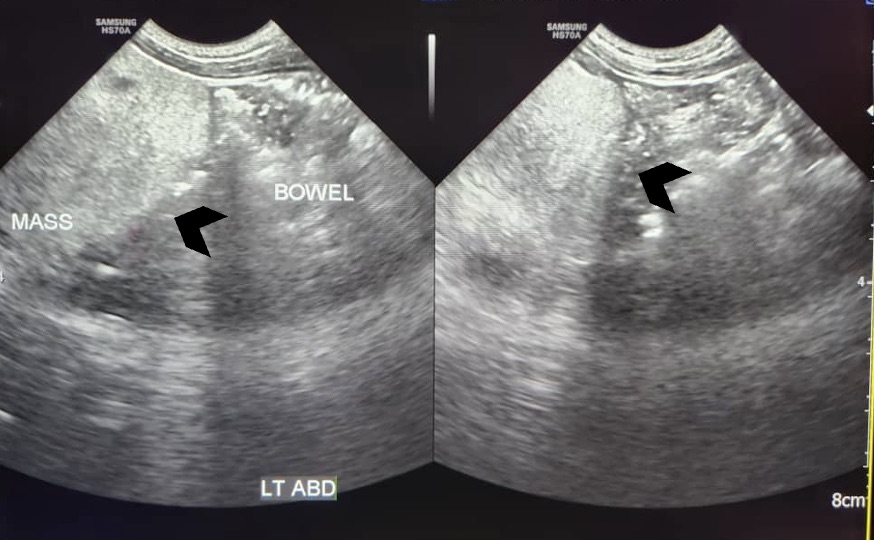

Abdominal ultrasound showed a large lobulated hyperechoic mass occupying abdomen and pelvis (black arrowhead)